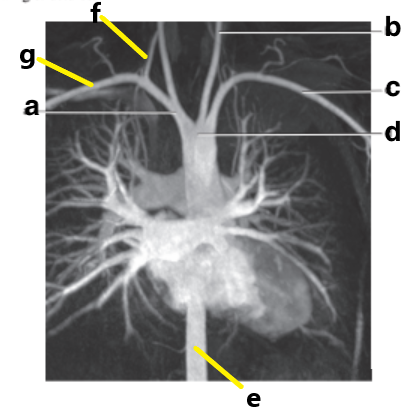

Left common carotid artery

Supplies blood to the left side of the neck and head.

Left subclavian artery

Supplies blood to the left upper extremity

Brachiocephalic trunk

Divides into the right common carotid and right subclavian arteries

Which letter is the Left common carotid ?

b

Which letter is the left subclavian artery ?

Which letter is the Right common carotid artery ?

d

What is letter a ?

Which letter is the right subclavian artery ?

g

c